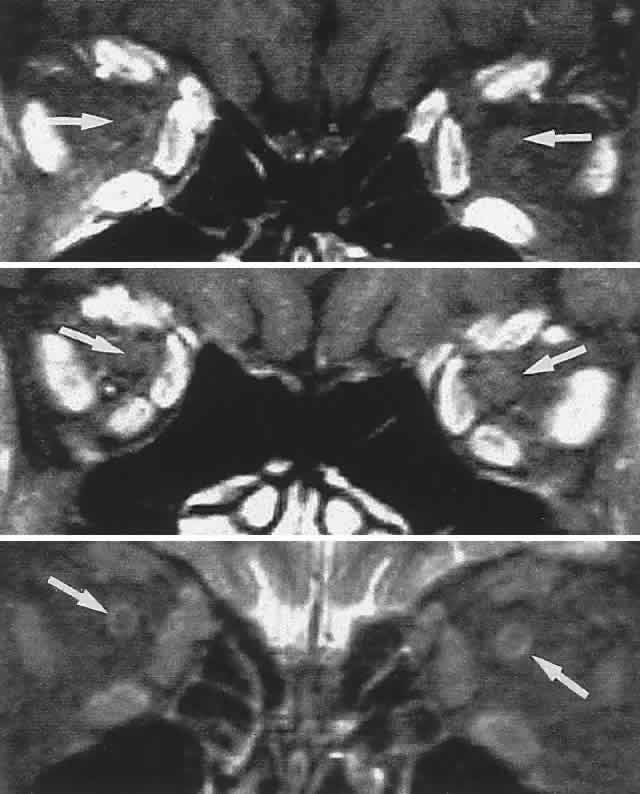

Orbital pseudotumor and the Tolosa-Hunt syndrome are likely the same process, varying only in that the idiopathic inflammation involves predominantly the orbit in the former and predominantly the superior orbital fissure and/or the anterior cavernous sinus in the latter. Idiopathic inflammation is a diagnosis of exclusion, made only in a fairly circumscribed clinical context, and when other pathologic processes have been ruled out. In this regard, contrast-enhanced CT scan or MRI shows diffuse infiltration or focal lesions, usually with notable enhancement of the posterior wall of the globe (Fig. 15). With proper orbital imaging and ultrasonographic assessment as diagnostic procedures, tissue biopsy is rarely necessary, and the response to systemic corticosteroid administration is usually dramatic, if not diagnostic (see also Volume 2, Chapter 12).

Fig. 15. Contrast-enhanced computed tomography (CT) scan in patient with painful ophthalmoplegia, lid swelling, and proptosis. In unilateral case, note enhancing envelope of thickened sclera (arrows) on coronal (A) and axial (B) sections of left globe. C. Bilateral orbital pseudotumor shows shaggy infiltration of orbital soft tissues (arrows) surrounding globes and optic nerves.